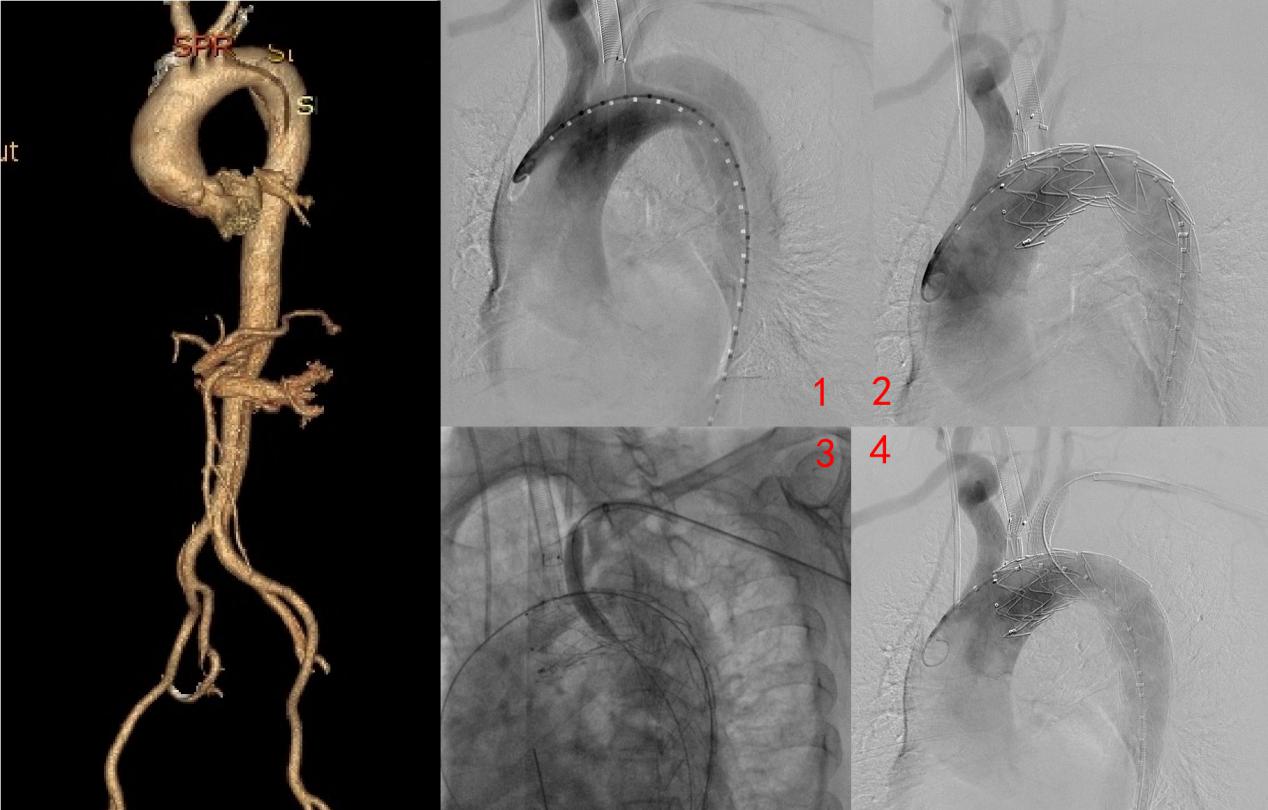

术中,通过造影确认主动脉内膜破裂口和真假腔情况(图1),释放支架主体并将分支支架引入左颈总动脉(图2)。造影定位确认后,穿刺针配合8F FUSTAR可调弯鞘同轴送入左锁骨下动脉,进行原位开窗;开窗成功后通过加硬导丝顺次送入Boston Mustang(4*40mm及8*40mm)进行扩张(图3)。扩张后置入VIABAHN (10*50mm)覆膜支架。造影显示,患者主动脉夹层隔绝良好,未见内漏;左颈总动脉分支支架及左锁骨下动脉开窗支架位置及形态良好,血流通畅(图4)。